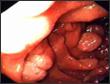

B/- Causes organiques coliques

• Les signes d’orientation:

- Syndrome rectal

- Sang/ glaires

- douleur du cadre colique et fosses iliaques

- Le retentissement peut être sévère (» MA)

• Diagnostic:

Coloscopie (Bx systématiques)

- RCH: ATCD familiaux, manifs extra intestinales Atteinte rectale constante, lésions continues

- Maladie de Crohn ATCD familiaux, manifs extra intestinales lésions anales, atteintes segmentaires Histo: granulome tuberculoïde, fissurations

- Amibiase Sd dysentérique, ulcérations « coup d’ongle » Parasitologie selles et Bx